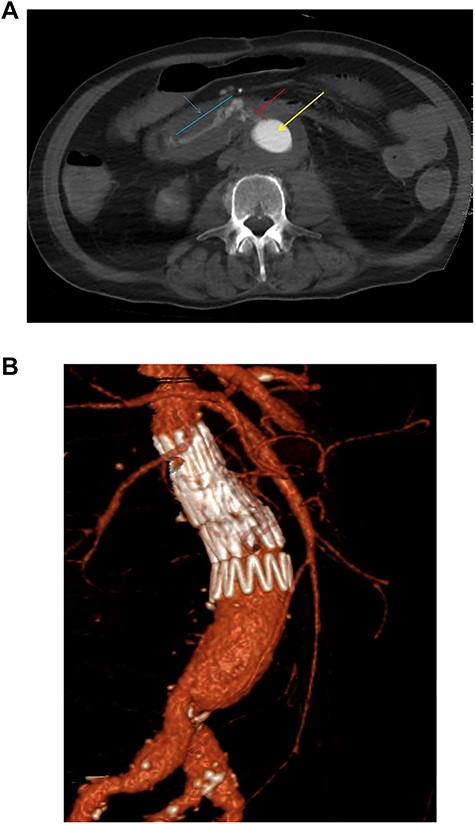

The second case is a 75-year-old gentleman with a background of ulcerative colitis who underwent an elective open tube graft repair for an 8 cm inflammatory aneurysm. In retrospect, inflammatory features are seen to extend distally to the iliac bifurcation on initial imaging (Fig. 2a). Thus, the patient may have benefited from the management of this at the initial surgery.

(a) Preoperative coronal thick slice of a CT with IV contrast in the arterial phase shows aneurysmal aorta with normal calibre common iliac arteries; however, inflammatory change around the aortic aneurysm is seen extending into the proximal iliac bifurcation (blue outline); (b) axial slice of a CT with IV contrast in the arterial phase shows aneurysmal common iliac arteries (red arrow), a clear saccular bulge (blue outline) into an adhered loop of small bowel (orange outline and arrow); the site of the fistulation.